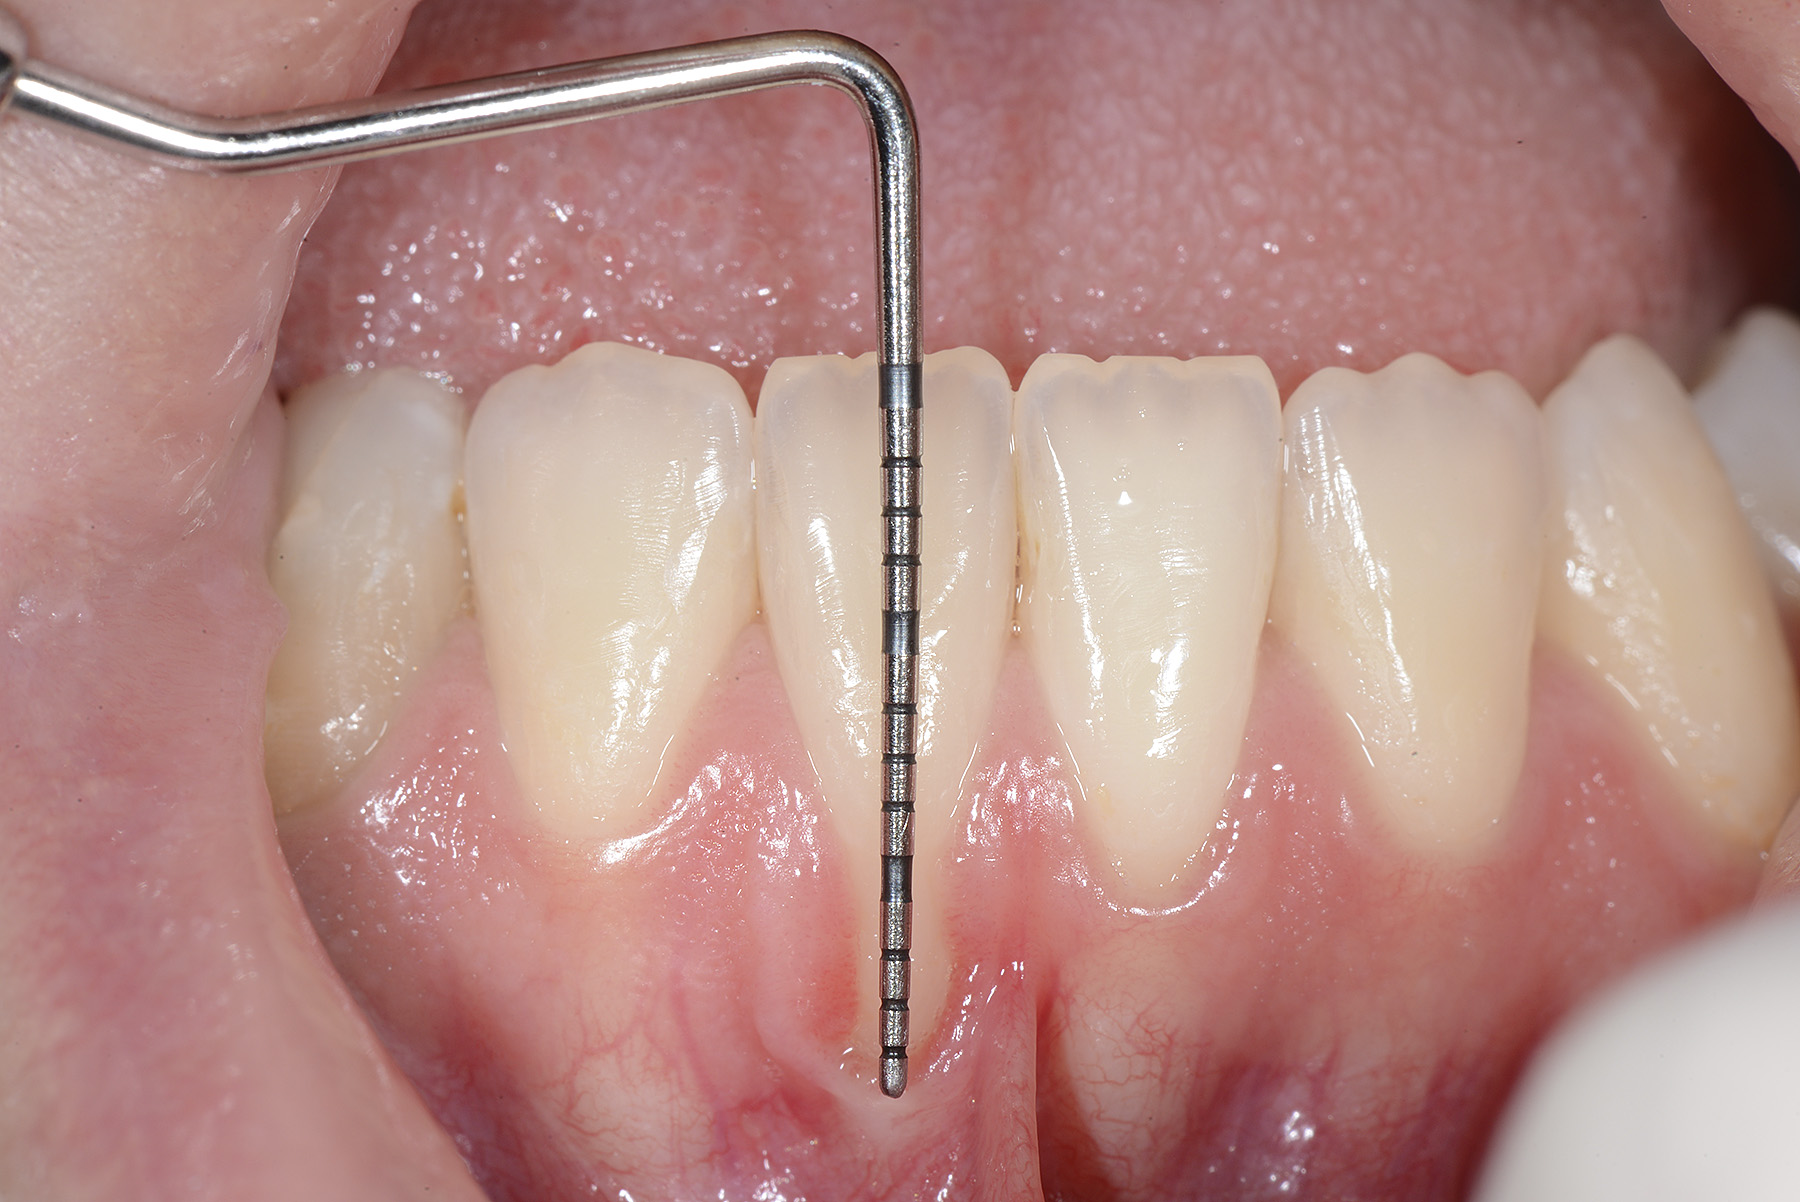

PREMESSA: in seguito all’estrazione dell’incisivo laterale superiore di destra, resasi necessaria per cause batteriche, si decide di affrontare il caso con il posizionamento di un impianto in sostituzione dell’elemento mancante dopo guarigione del sito infetto. Con tecniche rigenerative sia dei tessuti ossei mancanti a causa dell’infezione pregressa, sia dei tessuti gengivali che appaiono inizialmente troppo spostati in alto, si ripristina una corretta morfologia delle parabole (contorni) gengivali e delle papille interdentali (triangoli di gengiva tra due denti vicini).

Vengono utilizzati 2 tipi di provvisori: il primo, cementato ai denti vicini, viene utilizzato dal momento dell’estrazione del dente fino ad impianto osteointegrato (circa 6 mesi); il secondo, avvitato direttamente all’impianto, ha una funzione di prova estetica ma soprattutto di guida per la maturazione dei tessuti gengivali peri-implantari portandoli verso la maturazione completa prima di posizionare la corona finale in disilicato di litio.